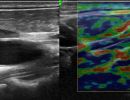

Η Ελαστογραφία αποτελεί ένα εξαιρετικά χρήσιμο εργαλείο στο Υπερηχογράφημα Λεμφαδένων Τραχήλου. Με την Ελαστογραφία, μπορούμε να αξιολογήσουμε την ελαστικότητα των λεμφαδένων, βοηθώντας έτσι στη διάκριση μεταξύ καλοήθων και διηθημένων λεμφαδένων. Αυτό είναι ιδιαίτερα σημαντικό στη διαδικασία της διάγνωσης.